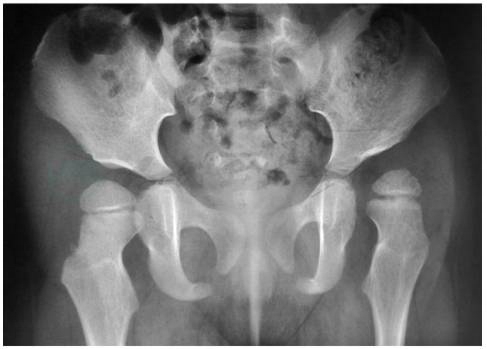

(1)正常骨盆正位片;(2)左侧髋关节脱位:股骨头位于Pekin’s方格的外上象限,髋臼角大,Shenton线不连续

图8 左侧髋关节脱位、右侧髋臼发育不良